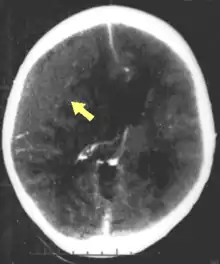

Movement disorders that may develop after TBI include tremor, ataxia (uncoordinated muscle movements), spasticity (muscle contractions are overactive), myoclonus (shock-like contractions of muscles), and loss of movement range and control (in particular with a loss of movement repertoire).[89][147] The risk of post-traumatic seizures increases with severity of trauma (image at right) and is particularly elevated with certain types of brain trauma such as cerebral contusions or hematomas.[138] People with early seizures, those occurring within a week of injury, have an increased risk of post-traumatic epilepsy (recurrent seizures occurring more than a week after the initial trauma).[148] People may lose or experience altered vision, hearing, or smell.[11]